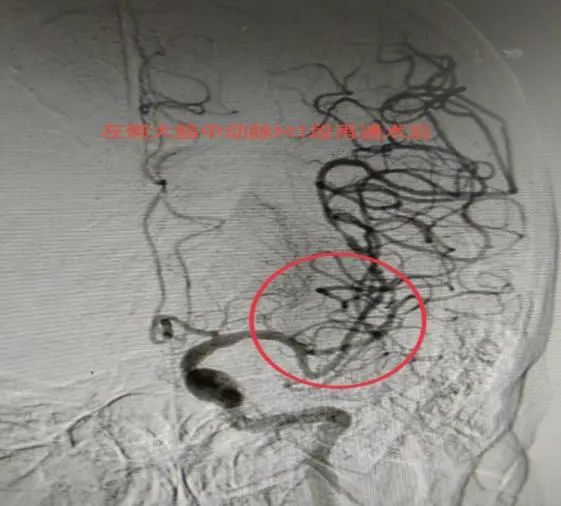

龙江医院自2020年起启动“卒中中心建设”,以多学科协作模式为基础,打造了一支由神经内科、外科、综合介入科专业力量,联动急诊医学科、检验科、医学影像科、超声科、药剂科、康复医学科等多学科协作的“脑卒中救治团队”,24小时随时待命,缩短脑卒中患者入院检查、治疗的时间。

卒中中心的流程不断优化,卒中救治的关键时间节点持续性改善,救治水平和能力不断提升。2021年11月成功创建“防治卒中中心”,2023年11月成功创建“综合防治卒中中心”,至今2025年成功创建“三级医院卒中中心”建设单位。

在各级领导的高度重视及大力支持下,医院不断强化内部管理,规范卒中绿色通道流程,定期召开质控会议,持续优化救治流程,同时,医院规范了卒中救治功能分区,设置清晰的标识与指引,整合院前急救系统与院内绿色通道,定期召开质量分析会和典型病例专题讨论会,组织开展卒中救治培训,完善一体化协同救治体系,不断提高对卒中患者的救治能力。